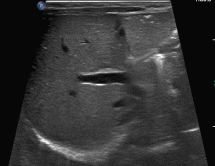

行超声检查,发现一些不一样的声像图表现:

图1~2:腹部探查,见些许点状高回声沿着肠壁朝一定方向快速移动,轨迹如“过山车”一般。

图4:肝区探查,见大量点状高回声相互簇拥着通过门静脉主干,涌入肝内;与此同时,可见肝左叶已散落分布着点、线状高回声,声影不明显。此外,肝周可探及少量不规则液性区。

PVG的超声表现,上面4幅动态图已然诠释,此外,有文献指出门静脉内流动的气泡可于频谱多普勒上间断出现毛刺状频谱,有一定特异性,可辅佐我们诊断PVG。